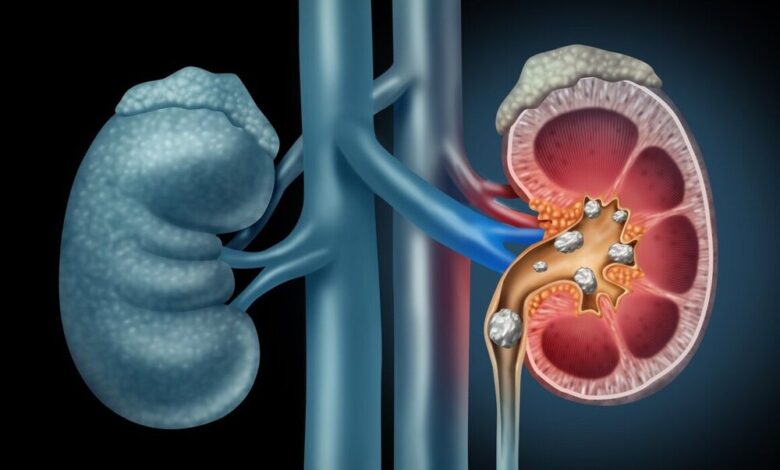

به گزارش خبرگزاری ایمنا، سنگ کلیه ذرات سختی هستند که در کلیه ها تشکیل می شوند و می توانند اندازه های مختلفی داشته باشند. این سنگ ها عمدتاً از مواد معدنی و نمک هایی مانند کلسیم، اگزالات و اسید اوریک تشکیل شده اند.

سنگ کلیه به دلیل تفاوت های آناتومیکی و هورمونی ممکن است در مردان شایع تر از زنان باشد. این وضعیت می تواند عوارض و مشکلات خاصی ایجاد کند.

حبیب الله موسوی بهار متخصص اورولوژی در گفت و گو با خبرنگار ایمنا با بیان اینکه سنگ کلیه در مردان دو برابر زنان دیده می شود، اظهار کرد: بیشترین بروز سنگ کلیه در سنین 20 تا 40 سالگی است اما این بیماری در همه سنین حتی در نوزادان قابل مشاهده است.

موسوی بهار گفت: سنگ کلیه دارای علائم و نشانه هایی است، درد شدید در ناحیه کمر یا شکم که به ناحیه کشاله ران گسترش می یابد یکی از علائم ابتلا به سنگ کلیه است و بهتر است در هنگام بروز علائم بیماری به پزشک مراجعه و از خود درمانی خودداری کنید.

متخصص اورولوژی بابیان اینکه نوشیدن مایعات کافی در دفع سنگ کلیه موثر است، تصریح کرد: مصرف برخی داروها علاوه بر نوشیدن مایعات می تواند به کاهش درد و کنترل حالت تهوع کمک کند. اگر وضعیت بیمار نامطلوب باشد، ممکن است نیاز به شکستن سنگ و جراحی باشد.